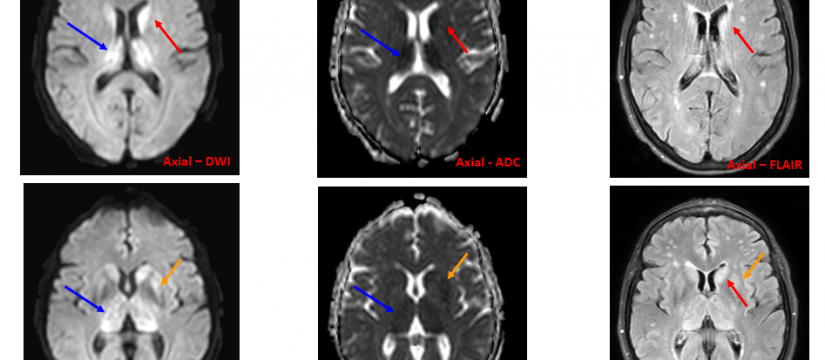

Mujer de 69 años de edad, con un cuadro de 7 meses de inestabilidad cefálica y de la marcha. Se realiza una RM craneal inicial, que es normal. Progresivamente, la síntomatología empeora, añadiéndose desorientación, alucinaciones, mioclonías y deterioro cognitivo. Se repite RM craneal por empeoramiento clínico progresivo.